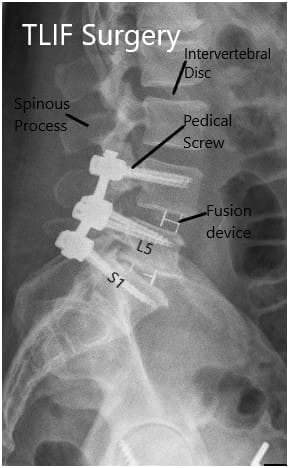

Intraoperative Fluoroscopic Images.

Postoperative X-ray in AP and Lateral views.